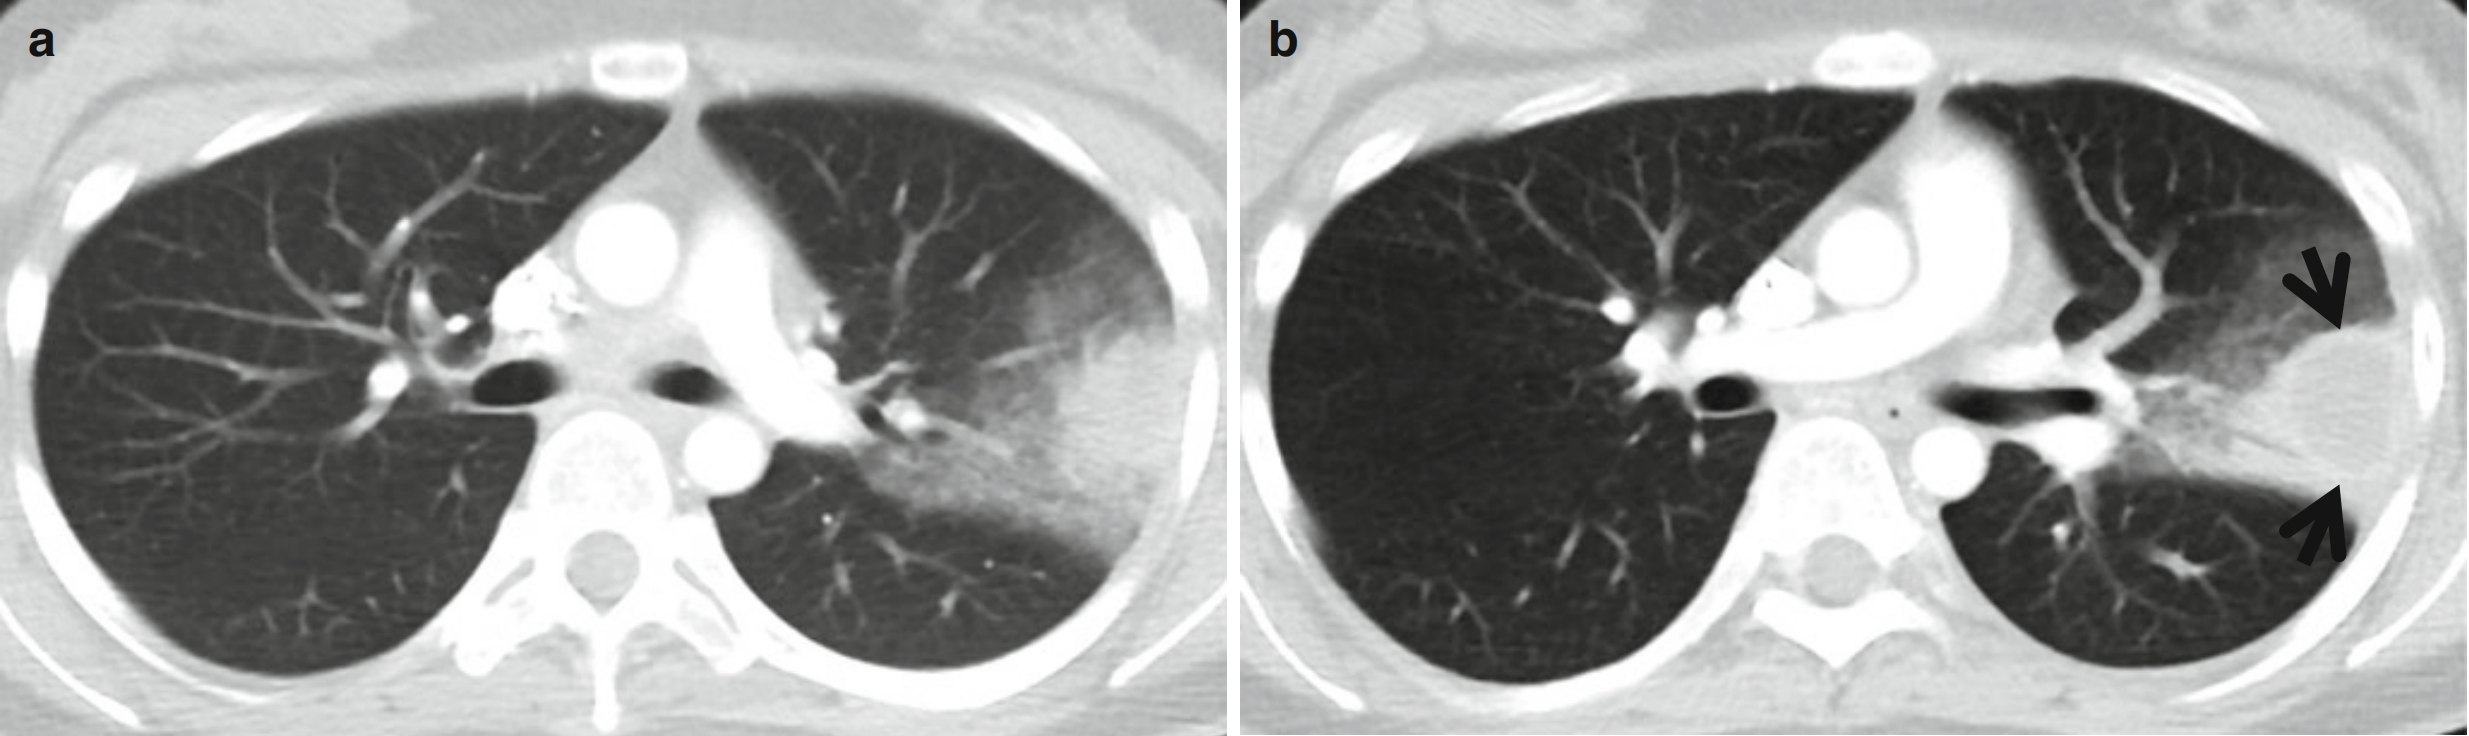

图1 反晕征。女,55岁。哮喘和慢性嗜酸细胞性肺炎患者。(a~c)薄层CT扫描(层厚=1.5 mm)肺窗分别于主动脉弓上层面(a)、主动脉弓层面(b)和奇静脉弓层面(c)示双肺多发局灶性GGO。请注意双肺上叶的反晕征(中央GGO被大致完整的环状实变影包围)(箭头所示)。

(a,b)薄层CT扫描(层厚=2.5mm)肺窗分别于肝上下腔静脉水平(a)和右膈顶水平(b)示双肺多发磨玻璃密度病灶,并可见反晕征(箭头所示)。